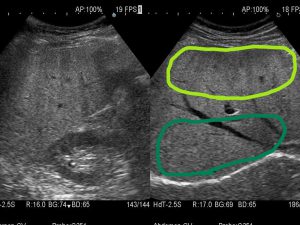

肝臓を占拠する!!パート1~できもの 悪くないもの 」腹部超音波検査 Vol.3 – みどり病院神戸市、明石市、循環器、透析。